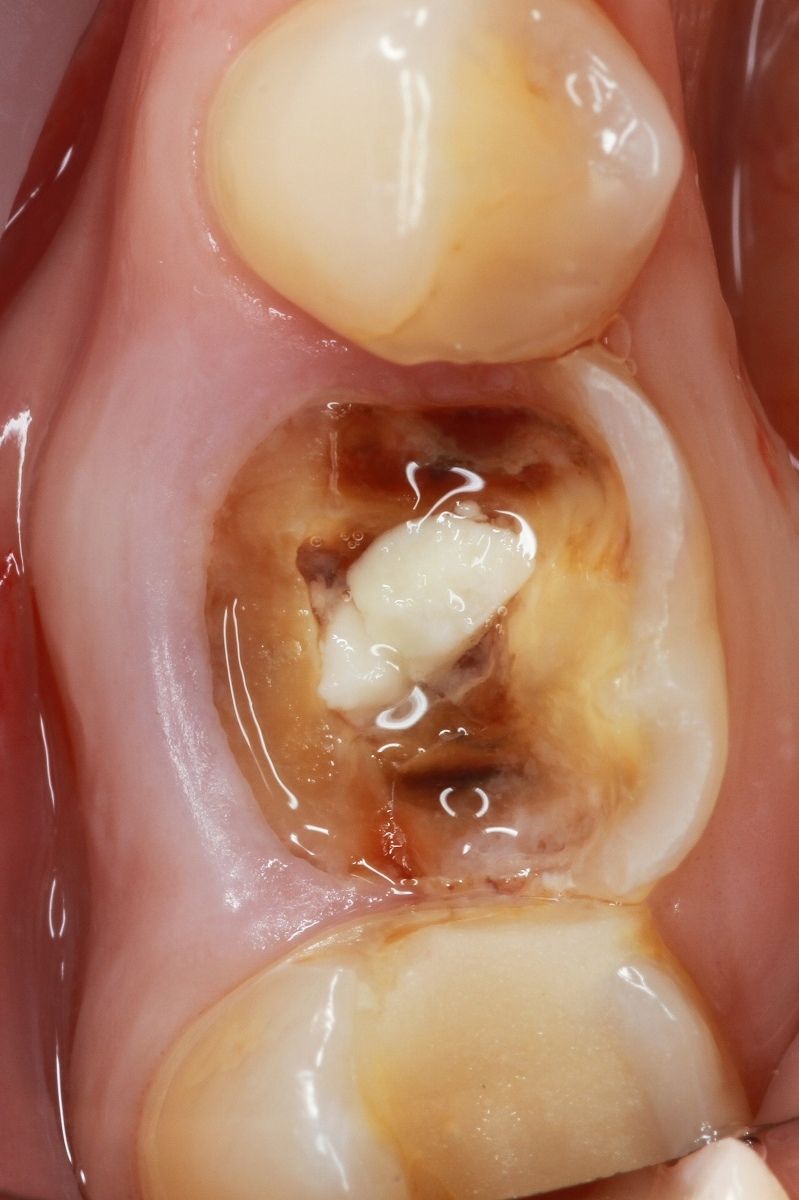

• we remove teeth, agreed in the treatment plan.

• if necessary, we perform bone and gingival grafting

• we install implants

Implantation immediately after careful tooth extraction is the best way to save tissue.